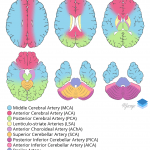

- Hypodensity with loss of gray-white differentiation in the right PCA territory, including the right occipital lobe and ventrolateral right thalamus

- Right PCA territory infarct